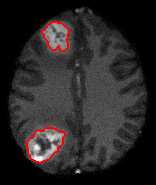

Single Seed Delineation of Brain Tumor using Multi-thresholding, Information Sciences, vol. 330, pp. 88–103, 2016.

©Elsevier (IF: 4.22)(Code)